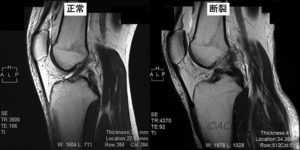

前十字靱帯(ACL)とは何ですか?

膝の 2 つの主要な靱帯は、前十字靱帯 (ACL) と後十字靱帯 (PCL)です。

これらの強力な組織帯は次のとおりです。

- 膝の真ん中で交差させる

- 大腿骨(太ももの骨)と脛骨(すねの骨)を接続します

- 膝関節を安定させ、前後の過度な動きを防ぎます。

ACLはPCLよりも損傷しやすいです。